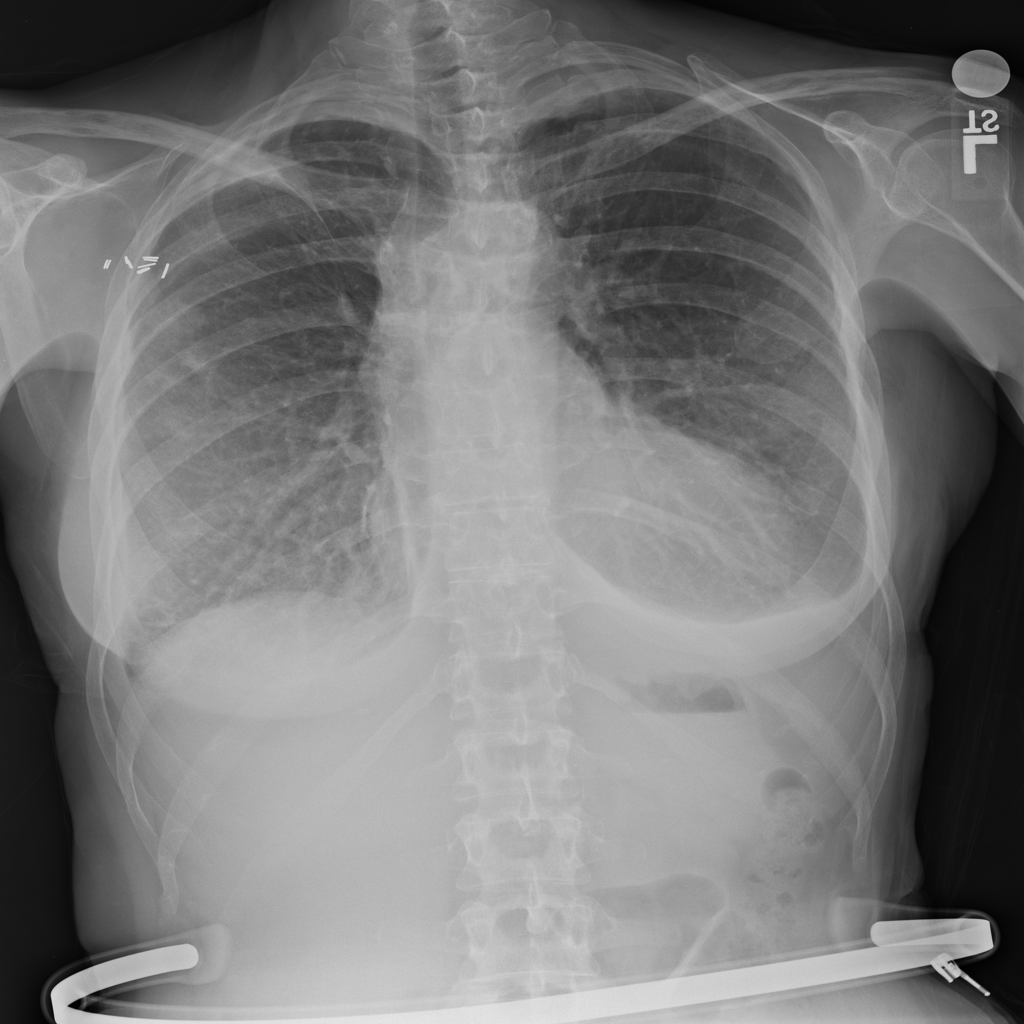

PAT-4639 · IMG-021Effusion

PAT-4639 · IMG-021

PA